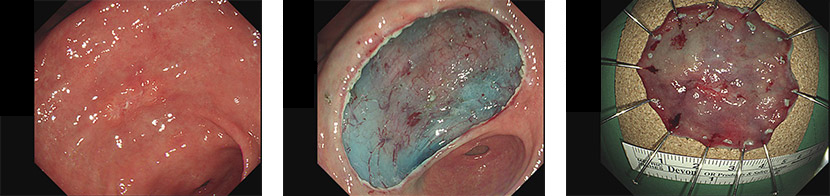

ESD(내시경적 점막하 박리술)란 내시경 하에서 위암이나 대장암의 병변부위를 벗겨내는 시술입니다.

급여기준을 충족한 경우 요양급여하며

종양 및 암의 크기는 내시경 육안 소견을, 림프절 전이 여부는 수술 전 검사 소견을 기준으로 적용합니다.

1. 위

1) 점막에 국한된 궤양이 없는 2cm 이하의 분화형 조기암

2) 1.5cm 이상인 선종, 이형성증

3) 섬유화를 동반한 선종

4) 점막하 종양

2. 식도

1) 절제된 조직이 원주의 2/3 이하를 침범하는 분화형 조기암

3. 결장, 직장

1) 점막에 국한된 궤양이 없는 5cm 이하의 분화형 조기암

2) 2cm 이상의 측방발육형 종양(측방으로 자라나가는 종양)

3) 2cm 이상의 무경성 용종(잘록한 목이 존재하지 않는 용종)

4. 기타

1) 림프절 전이가 없는 분화형 조기암: 위, 식도, 결장, 직장

2) 점막에 국한된 궤양이 없고 2cm 이하이며 림프절 전이가 없는 미분화형 조기암: 위

3) 점막하 종양: 식도, 결장, 직장